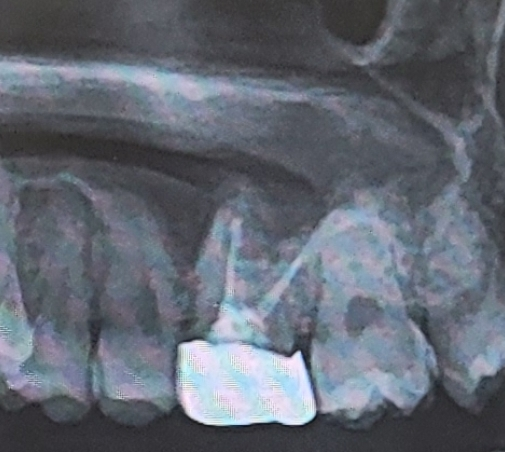

크라운 발치했는데 드라이소켓 예방하는 방법이 있을까요?

신경치료 2번 한 곳인데 뿌리도 상악동 가까이에 있었고, 3등분 해서 뽑아냈는데 피가 거의 안나요

이럴 경우 안에 염증이 생겨서 드라이소켓 가능성이 있다고 하더라고요..

• 1번 째 사진